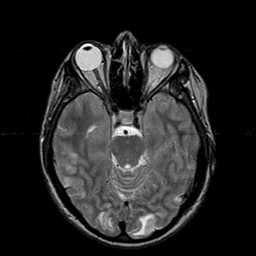

Hypertensive Encephalopathy, overlay -- Slice #8

[Home][Help][Clinical] Slice 8